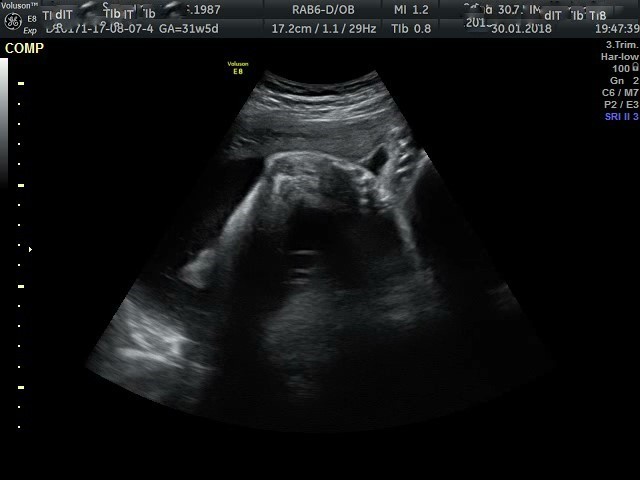

Witam jak impretować badanie usg "...Nieco nadmierne przygięcie obu stópek..."Badanie robione 33 tydzień ciąży.Czy to będą SKS ?? Proszę o odpowiedz

• stopa.jpg

stopa.jpg

58 KB · Wyświetleń: 3 757

Malinka22 kurcze wydaje mi się że lewa stopka wygląda jak SKS ale nie wiem na 100% ponieważ ja się dowiedziałam po porodzie a lekarz nic ci nie mówił?może wypowiedzą się dziewczyny które też się w ciąży dowiedziały?zdrówka życzę bd dobrze [emoji8]